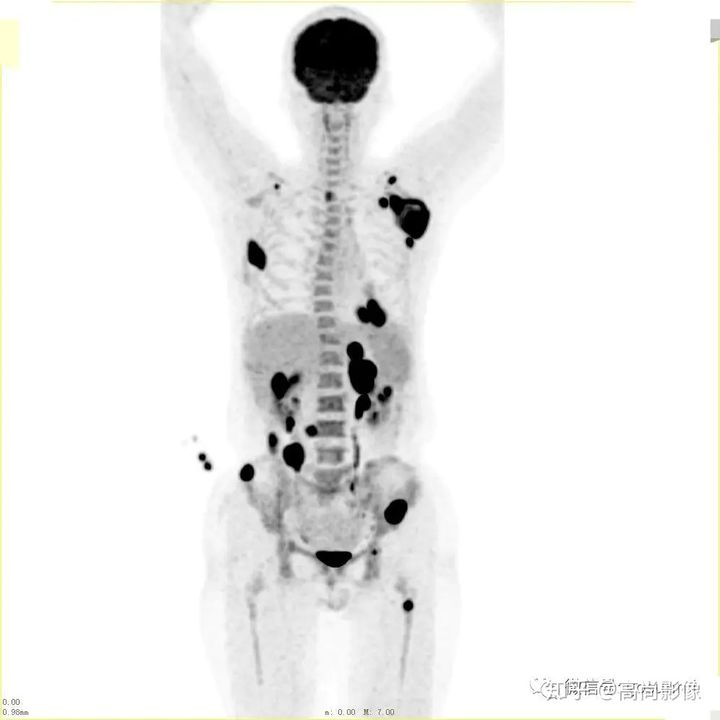

方大爺?shù)腜ET/CT結(jié)果強烈提示肺癌伴全身多發(fā)轉(zhuǎn)移,已經(jīng)失去手術(shù)機會,但仍有繼續(xù)化療的機會。

與方大爺有類似病情的一位患者,化療前后的PET/CT影像顯示,腫瘤得到了很好的控制。

肺癌化療前評估的MIP圖

(最大密度投影圖)

肺癌化療后評估的MIP圖

由此可見,惡性腫瘤化療前后的全身PET/CT評估有多重要,尤其對于惡性腫瘤患者來說,時間就是生命,早一天完善診斷,早一天得到正確的治療,預(yù)后就會更佳。